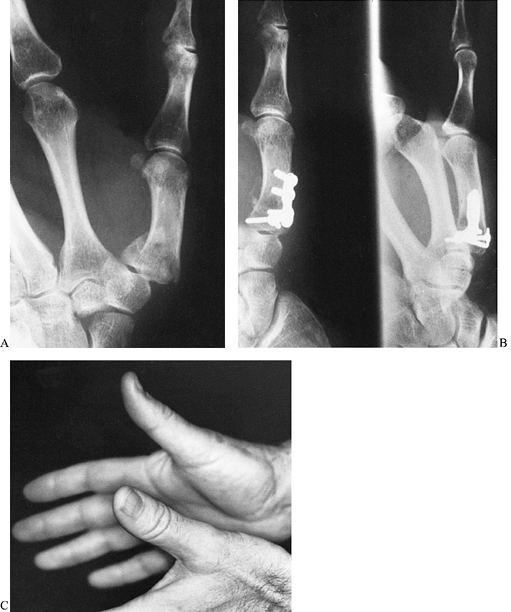

reconstruction (Fig. 40.12) (19).

![]() |

|

Figure 40.12. A 42-year-old man fell and sustained a closed intraarticular Rolando fracture of the base of his right dominant thumb. A: Anteroposterior radiograph shows the fracture configuration. B: The fracture was openly reduced and internally fixed with a 2.0-mm interfragmentary screw as well as a small L plate. C: The fracture healed, and the functional recovery was excellent.

joint while healing occurs (Fig. 40.13) (10).

Figure 40.13. A 30-year-old tool-and-die worker’s dominant thumb was caught in a lathe, causing extensive skeletal and soft-tissue trauma. A:

Anteroposterior radiograph shows a comminuted intraarticular fracture at the base of the metacarpal as well as a severe fracture of the proximal phalanx. B: Following repair of the flexor pollicis longus and the radial digital nerve and artery, an open reduction and internal fixation of the base of the metacarpal was accomplished. The impacted articular fragments were reduced, held with 0.035-mm Kirschner wires, and supported by distal radius cancellous bone graft. A mini-external fixation unit was placed to prevent settling of the joint reconstruction, to maintain the first webspace, and to maintain reduction of the proximal phalanx fracture. C: Rehabilitation of the hand progressed with the fixator in place. |